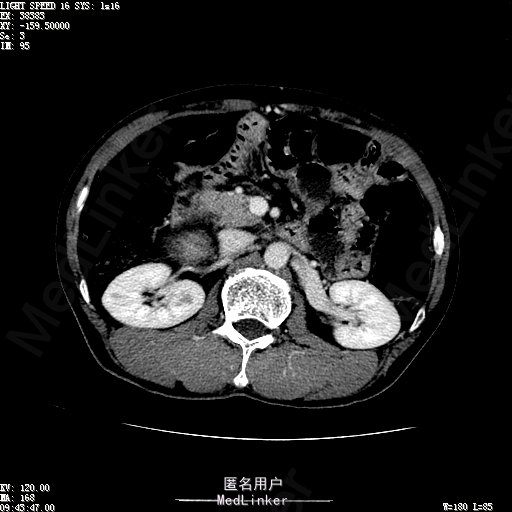

查体:体温36.4℃,脉搏76次/分,呼吸18次/分,血压110/70mmHg。神志清晰,发育正常,营养中等,体位自如,表情安静,慢性病容,检查合作。皮肤粘膜颜色正常,无瘀点、紫癜,有肝掌,无蜘蛛痣,无水肿,毛发的生长与分布正常。浅表淋巴结浅表淋巴结未触及肿大。无巩膜黄染,结膜正常。口唇红润,粘膜正常,舌正常,牙龈正常,扁桃体无肿大,无咽部充血。颈部外形对称,颈静脉正常,肝颈静脉回流征阴性,气管居中。甲状腺正常,无颈部血管杂音。胸部形态正常,呼吸运动平稳规律,无呼吸困难,肋间隙正常。触诊语颤正常,无胸膜摩擦感,肺下界位于右锁骨中线第六肋间。呼吸音正常,未闻及干湿啰音,无胸膜摩擦音。无心前区隆起,心尖搏动正常,心率:76次/分,心律齐,心音正常,无杂音,无心包摩擦音。无大动脉及周围血管征,无奇脉及交替脉,无水冲脉,无枪击音,腹型对称,无腹壁静脉曲张,未见胃肠型及蠕动波,无瘢痕,脐部正常。无压痛,无反跳痛,无腹肌紧张,无腹部包块。肝未触及,Murphy征阴性,脾未触及,肾未触及,无移动性浊音。无肝区叩击痛,无肾区叩击痛,无脾区叩击痛。肠鸣音正常4次/分,无气过水声。外阴及肛门:未查。四肢正常,关节正常,无下肢水肿,无下肢静脉曲张,无杵状指趾。 辅助检查:彩超:肝表面欠光滑,肝内占位5.2*5厘米 ct如下图

诊断:乙肝肝硬化 代偿期 原发性肝癌。 患者病史明确,目前化验转氨酶轻度升高,说明有活动性肝损伤,白蛋白降低提示肝脏合成代谢功能下降,AFP从一年前至今逐渐升高,提示活性肿瘤细胞增多。CT所见明确诊断肝癌,并有周围卫星灶,应近期行TACE治疗。 处置:DSA下肝动脉造影及TACE 手术简要经过:患者平卧位,术区皮肤消毒,铺手术巾,2%利多卡因局麻后,Seldinger法穿刺右股动脉,入血管鞘,5F猪尾管腹主动脉造影,超滑导丝yidao5F RH管腹腔干、肠系膜上动脉、左肾动脉分别造影,腹腔干造影时,见肝右叶7-8处小结节样肿瘤染色,未见外凸生长较大病灶染色。微导管超选肝右动脉注入三氧化二砷碘油混悬液10毫升,横结肠遮挡部位见较大病灶有伞状碘油沉积。复查造影未在见肿瘤染色,拔出导管和血管鞘,穿刺处压迫止血,加压包扎。术毕。

患者术后8天来,无不适,无发热,无腹痛和腹胀,无恶心呕吐,食欲睡眠好,尿便正常。 查体:神志清,巩膜无黄染,心肺听诊无异常,腹软,无压痛,肝脾肋下未触及,移动性浊音阴性,双下肢无浮肿。 复查化验结果:丙氨酸氨基转移酶 116 U/L、天门冬氨酸氨基转移酶 41 U/L、胆碱酯酶 1995 U/L↓、总蛋白 56.3 g/L、白蛋白 25.9 g/L。白细胞计数 5.8 10^9/L、红细胞计数 3.18 10^12/L、血小板计数 175.0 10^9/L、*血红蛋白 83 g/L、血小板分布宽度 15.7 、血小板压积 0.175 %、*红细胞压积 24.6 %、平均红细胞血红蛋白 26.1 pg、平均红细胞血红蛋白浓度 337.0 g/L、平均红细胞体积 77.5 fL、平均血小板体积 10.0 fL、嗜碱性粒细胞百分比 0.4 %、嗜碱性粒细胞数量 0.02 10^9/L、中性粒细胞百分比 70.4 %、中性粒细胞数量 4.10 10^9/L、嗜酸性粒细百分比 2.1 %、嗜酸性粒细胞数量 0.12 10^9/L、单核细胞百分比 12.2 %、单核细胞计数 0.7 10^9/L、淋巴细胞数量百分比 14.9 %、淋巴细胞计数 0.9 10^9/L。甲胎蛋白 23564.00 ng/mL 患者术后第8天开始行FOLFOX6化疗。CT上可见明显碘油沉积,术后甲胎蛋白下降治疗有效。嘱患者术后必须定期复查